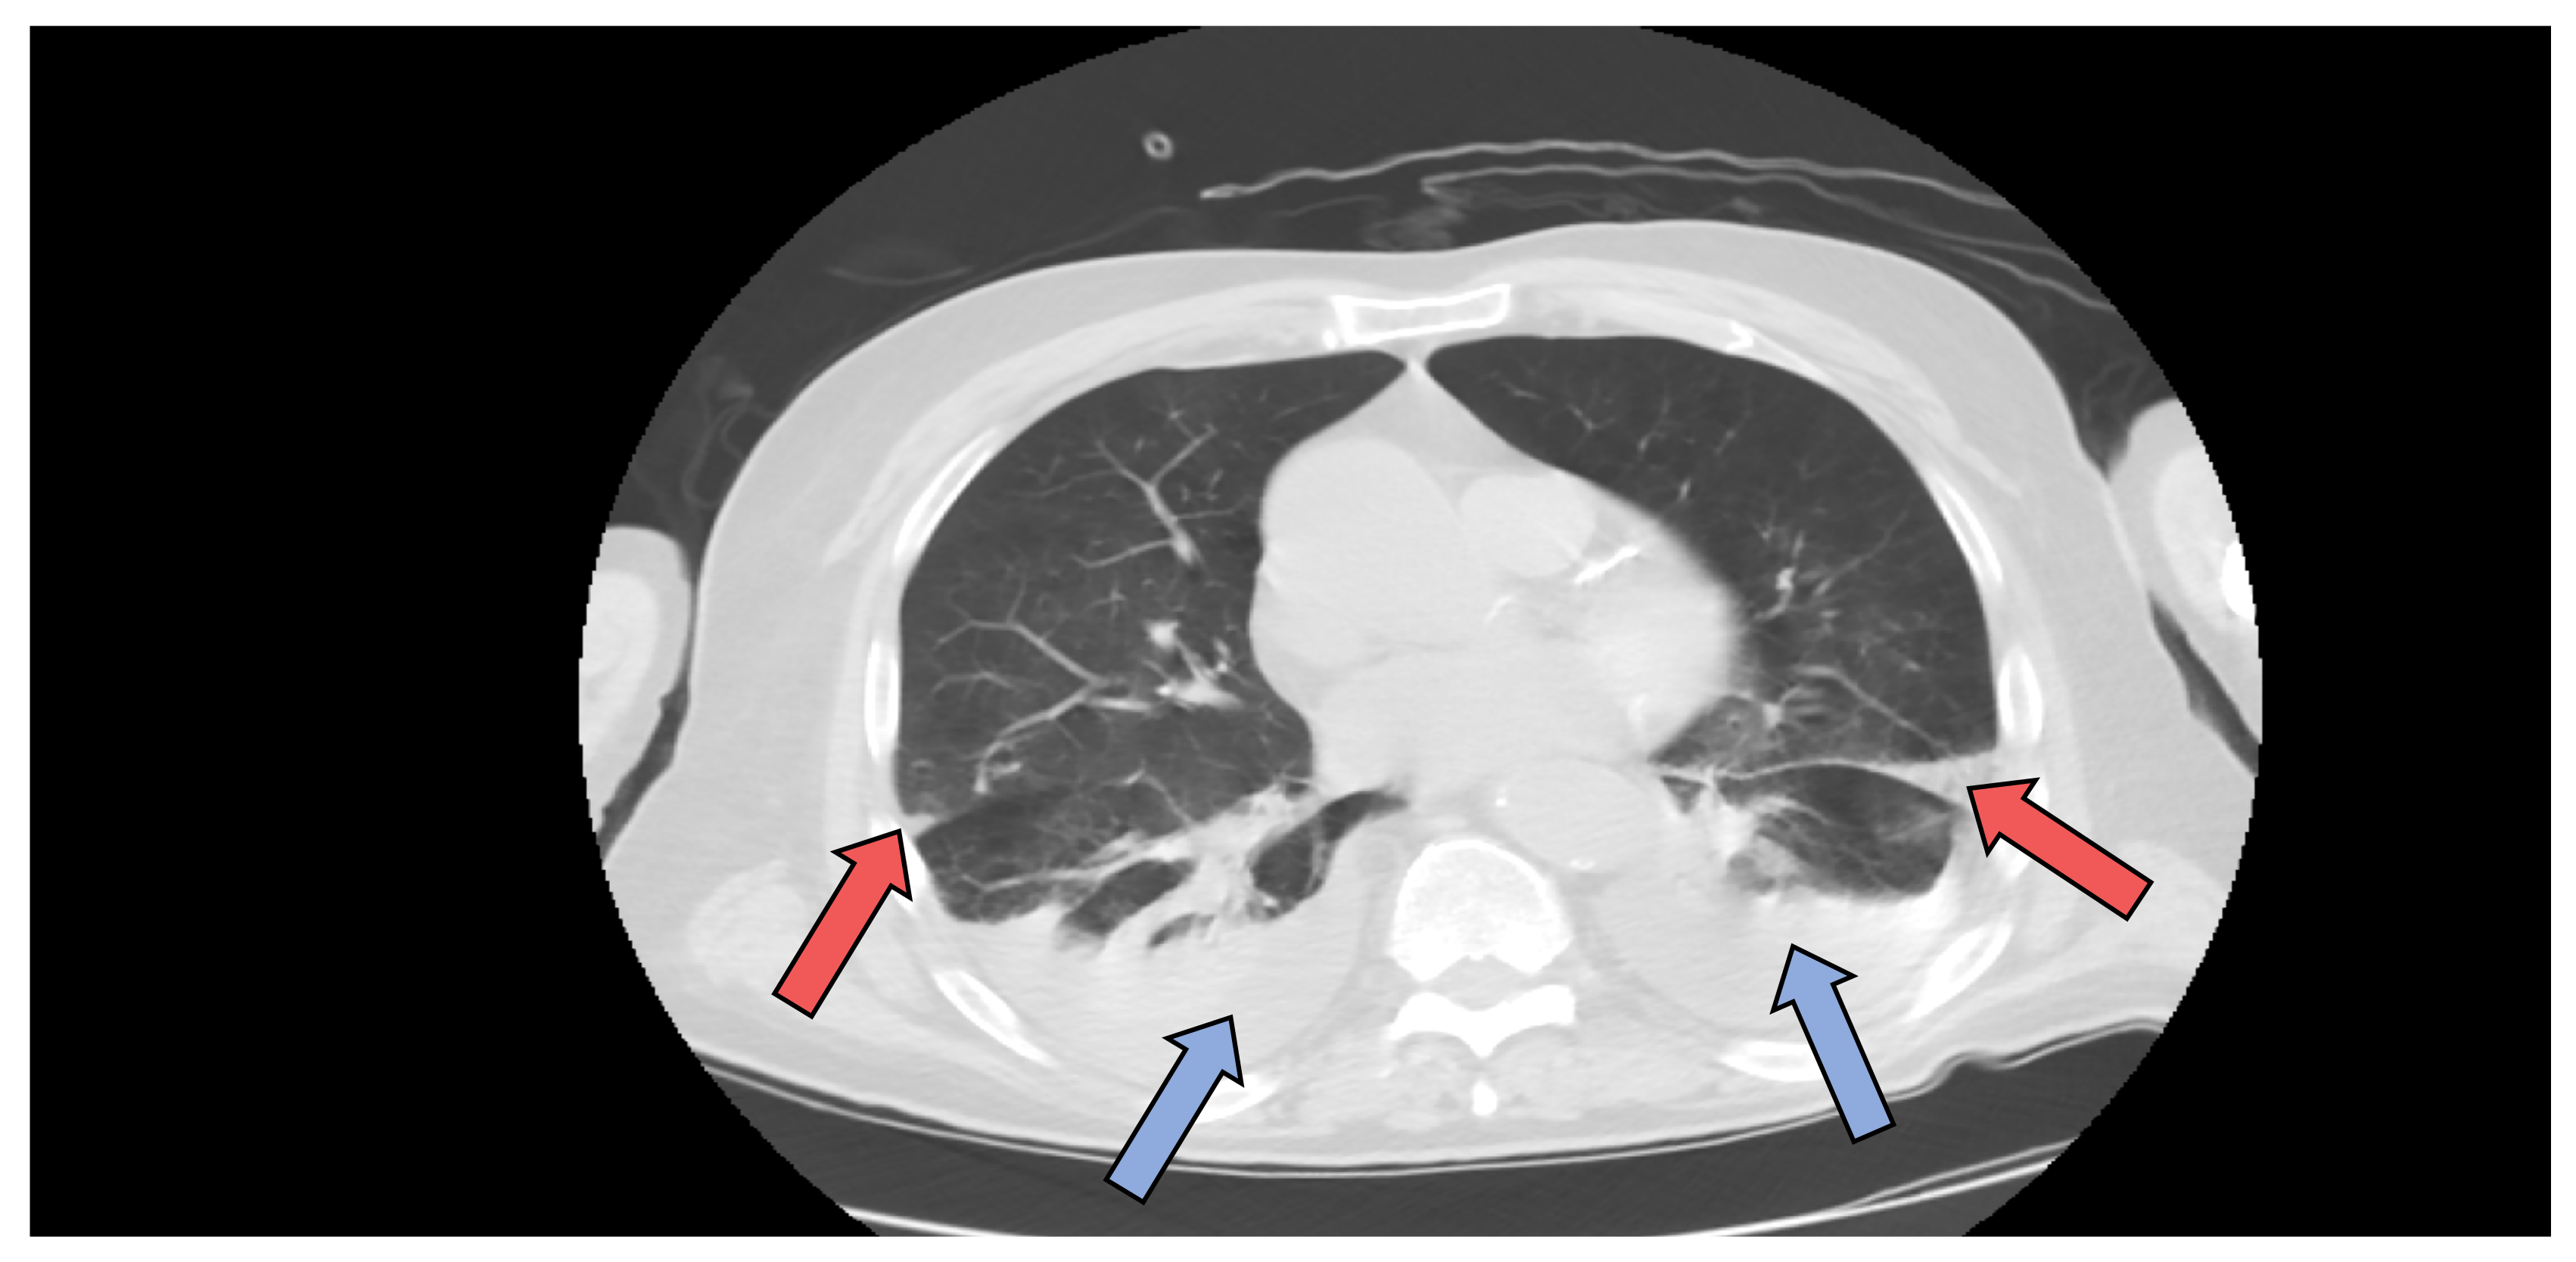

Due to the presence of COVID-19 infection, a native chest computer tomography (CT) was performed, which revealed bilateral pulmonary infarction (Figure 3 red arrows) and bilateral pleural effusion (Figure 3 blue arrows), but no signs of ground glass opacities characteristic of COVID-19 pneumonia. Lower limb deep venous ultrasound excluded deep vein thrombosis. The echocardiography did not show signs of high pressure in pulmonary arteries and troponins and NT-proBNP were in normal range, thus excluding a massive TEP.

Figure 3. Chest computer tomography (CT) axial view showing bilateral pulmonary infarction (red arrows) and bilateral pleural effusion (blue arrows).